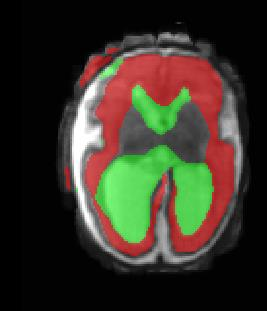

Limiting failures of machine learning systems is of paramount importance for safety-critical applications. In order to improve the robustness of machine learning systems, Distributionally Robust Optimization (DRO) has been proposed as a generalization of Empirical Risk Minimization (ERM). However, its use in deep learning has been severely restricted due to the relative inefficiency of the optimizers available for DRO in comparison to the wide-spread variants of Stochastic Gradient Descent (SGD) optimizers for ERM. We propose SGD with hardness weighted sampling, a principled and efficient optimization method for DRO in machine learning that is particularly suited in the context of deep learning. Similar to a hard example mining strategy in practice, the proposed algorithm is straightforward to implement and computationally as efficient as SGD-based optimizers used for deep learning, requiring minimal overhead computation. In contrast to typical ad hoc hard mining approaches, we prove the convergence of our DRO algorithm for over-parameterized deep learning networks with ReLU activation and a finite number of layers and parameters. Our experiments on fetal brain 3D MRI segmentation and brain tumor segmentation in MRI demonstrate the feasibility and the usefulness of our approach. Using our hardness weighted sampling for training a state-of-the-art deep learning pipeline leads to improved robustness to anatomical variabilities in automatic fetal brain 3D MRI segmentation using deep learning and to improved robustness to the image protocol variations in brain tumor segmentation. Our code is available at https://github.com/LucasFidon/HardnessWeightedSampler.